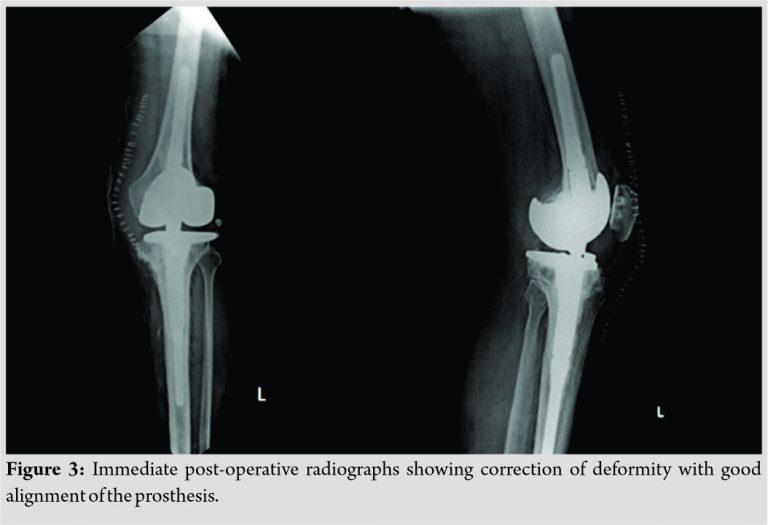

Immediate post-operative radiographs showed correction of the deformity with good position of the prosthesis (Fig. 3). Skin staples were removed after 2 weeks. The patient was followed up once every 2 weeks till 3 months. He was put on a long knee brace for a period of 3 months to maintain the knee in extension and followed-up once a month thereafter. At 1 year after the surgery, the patient had an extension lag of 5° (Fig. 4). Supervised physiotherapy was continued. The patient had knee flexion up to 120° without extension lag at 30 months follow-up (Fig. 5).